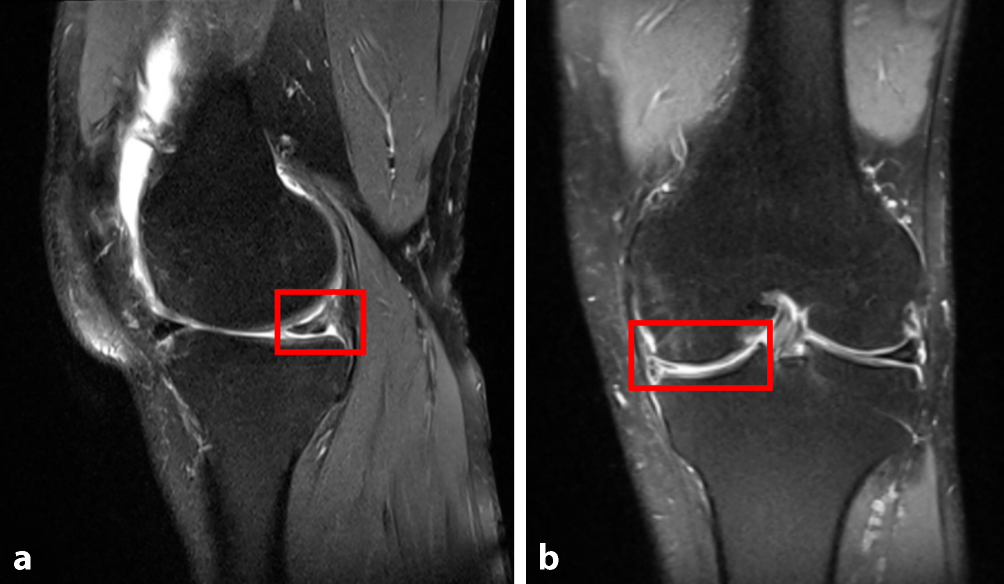

Anschließend wurde eine MRT-Untersuchung des linken Kniegelenks zur weiteren Abklärung der Beschwerden veranlasst. In der MRT-Bildgebung des linken Kniegelenks zeigten sich eine im Verlauf deutliche Volumenminderung des Innenmeniskushinterhorns sowie der Pars intermedia bei Z. n. Meniskusteilresektion mit kleiner fokaler an die Unterfläche reichender Rissbildung am Hinterhorn. Im Verlauf zunehmende Volumenminderung der chondralen Überzüge im medialen Kompartiment insbesondere am randständigen Condylus mit flauem initialen, subchondralem Ödem und kleine osteophytäre Ausziehungen (Abb. 2).

Abb. 2

MRT-Untersuchung des linken Kniegelenks in PD-TSE-FS-Sequenzen. a Die sagittale Schnittbildgebung zeigt eine fokale an die Unterfläche reichende Rissbildung am Hinterhorn, b die koronare Schnittbildgebung zeigt eine deutliche Volumenminderung des Innenmeniskus und Volumenminderung der chondralen Überzüge im medialen Kompartiment mit subchondralem Ödem